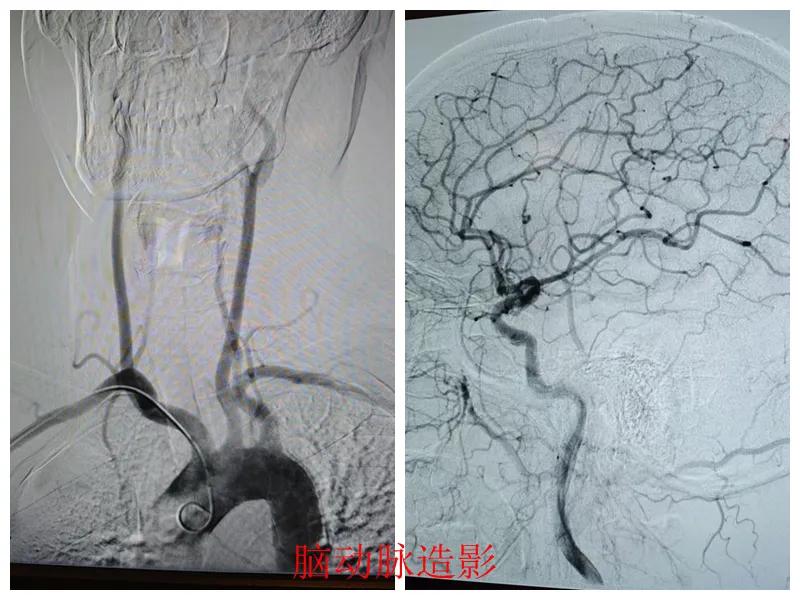

術(shù)前準(zhǔn)備完善后,在王瑾院長帶領(lǐng)下,心血管內(nèi)科主任李慧新、影像科主任宋貴良、副主任醫(yī)師趙進(jìn)科等緊密協(xié)作,成功為患者實(shí)施了冠狀動(dòng)脈造影及腦動(dòng)脈造影兩項(xiàng)檢查。冠狀動(dòng)脈造影結(jié)果提示:患者右冠狀動(dòng)脈慢性閉塞,腦動(dòng)脈造影提示腦血管多支狹窄病變。